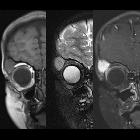

with a right orbital mass. Coronal T1 MRI without contrast of the orbits (left) and coronal T2 MRI (middle) shows a round soft tissue mass superior and lateral to the right orbit that is isointense on both sequences and that on coronal T1 MRI with contrast (right) is seen to enhance uniformly and intensely.The diagnosis was myofibroma.